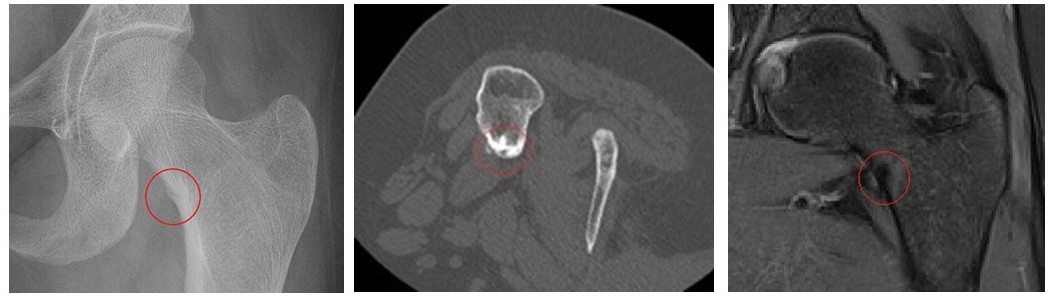

Поставянето на диагнозата често изисква комбинация от образни изследвания:

- Рентгенография – възможно е лезията да бъде пропусната при липса на изразена костна реакция. Когато е видима, се наблюдава зона с по-ниска плътност, оградена от склеротичен костен вал.

- Компютърна томография (КТ) – златен стандарт в диагностиката. Позволява ясно визуализиране на нидуса и централната склероза.

- Ядрено-магнитен резонанс (ЯМР) – може да покаже неспецифичен костен оток и да доведе до диагностични затруднения при до 35% от пациентите.

След проведени образни изследвания – рентгенография, компютърна томография и ядрено-магнитен резонанс – се установява малка лезия в областта на шийката на лявата бедрена кост, отговаряща на остеоид остеом.